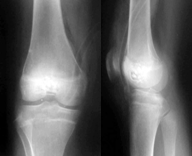

Интрамедуллярный остеосинтез с наднадкостничной аллопластикой перфоостом мы использовали в 12 случаях у 9 больных с несовершенным остеогенезом, что способствовало укреплению и увеличению костной массы оперируемого сегмента (рис.4, а –в).

Рис. 4. Б-ая Ш., 15 лет. Деформации нижних конечностей на почве несовершенного остеогенеза: а – рентгенограммы до операции; б – интраоперационная картина: корригирующие остеотомии левой бедренной кости, интрамедуллярный остеосинтез с наднадкостничной аллопластикой перфоостом; в – рентгенограммы после операции